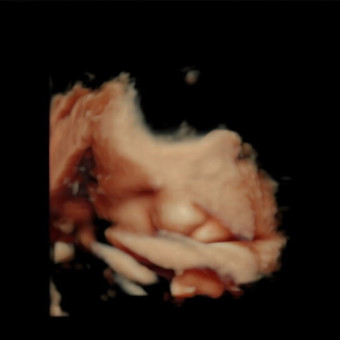

It's a boy! Sawyer will be here any day now and is already so loved! We will keep this open until he is 3 months old!